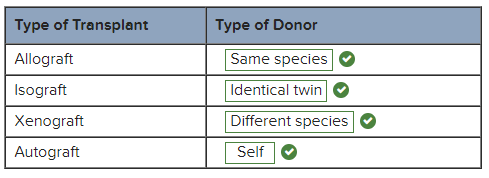

For each classification of transplant, indicate the correct type of donor.